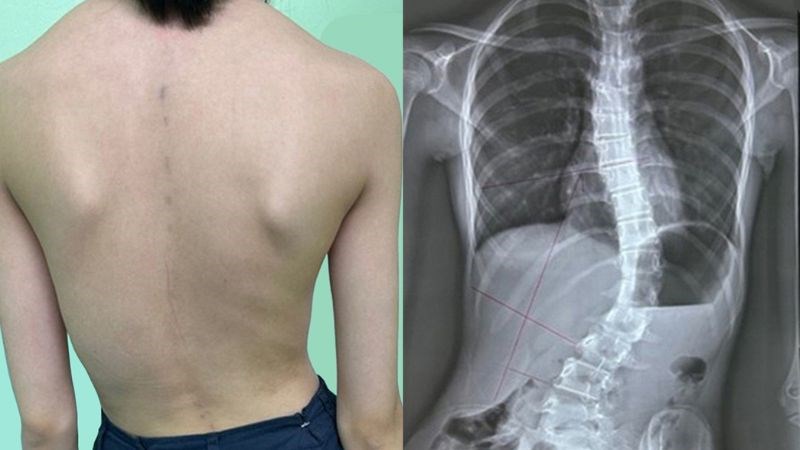

- Chứng cong vẹo cột sống, nhiều khả năng phát triển từ khi trẻ 6 tuổi.

Cong vẹo cột sống là dấu hiệu muộn thường gặp trong giai đoạn 4

- Chứng cong vẹo cột sống thường bắt đầu từ 6 tuổi và tiến triển nghiêm trọng dần theo thời gian.